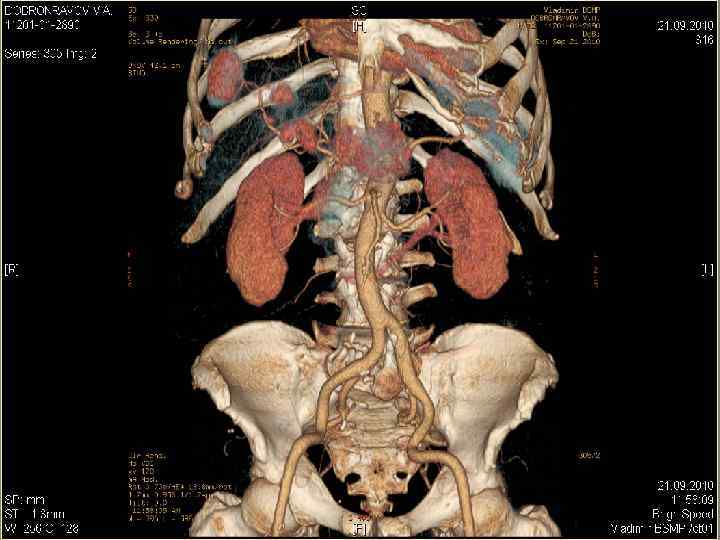

Диагностические возможности КТ-технологий: а сочетание опухоли (желтая), протоков (зеленые) и сосудов (синие – вены, красные –артерии), б – трехмерная реконструкция КТ-изображения у больной ХЦР (то же наблюдение), в – то же наблюдение – вид сзади (эффект «стеклянного объекта» ) – опухоль, сосуды и протоки «просвечивают» через ткань печени, г – виртуальная правосторонняя «резекция» печени. б а в г